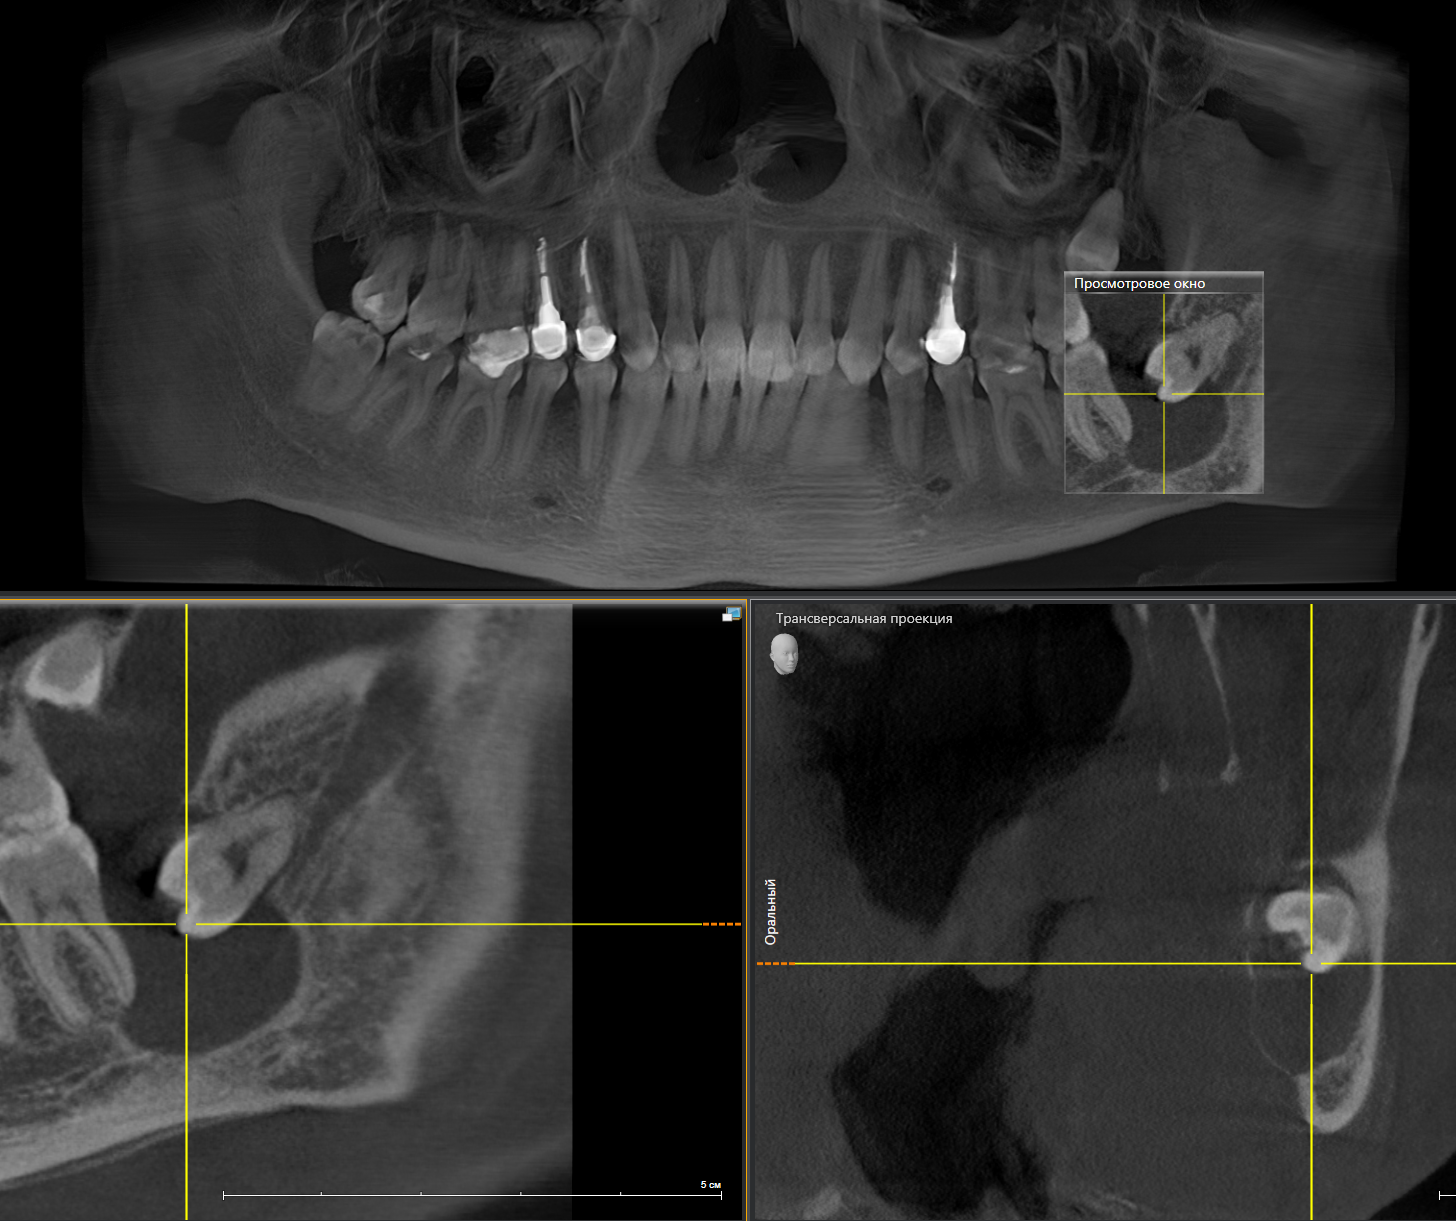

На прием пришла девушка с пожеланием восстановить удаленный ранее в другой клинике зуб на верхней челюсти справа. Ну что ж, без проблем. Направляю пациентку на компьютерную томографию для оценки ситуации. И вдруг я вижу «её» – притаившуюся в пазухе омерзительную восьмерку, которая, противно ухмыляясь, смотрит прямо на меня.

Кроме того, что она сама по себе противная, так еще она успела навредить 7му зубу.

Красным пунктиром отмечено разрастание фолликулярной кисты, которая распространилась в область корней зуба по соседству.

На панорамном снимке, сделанном после имплантации, хорошо видно, насколько высоко и неудачно она располагается:

Добрый вечер… А что это значит?... Прекрасно видно, что фолликулярная киста начала расти и оттеснять зуб мудрости дальше в пазуху, что несколько затрудняет его удаление. Блять, подумал я, надо было сразу удалять.